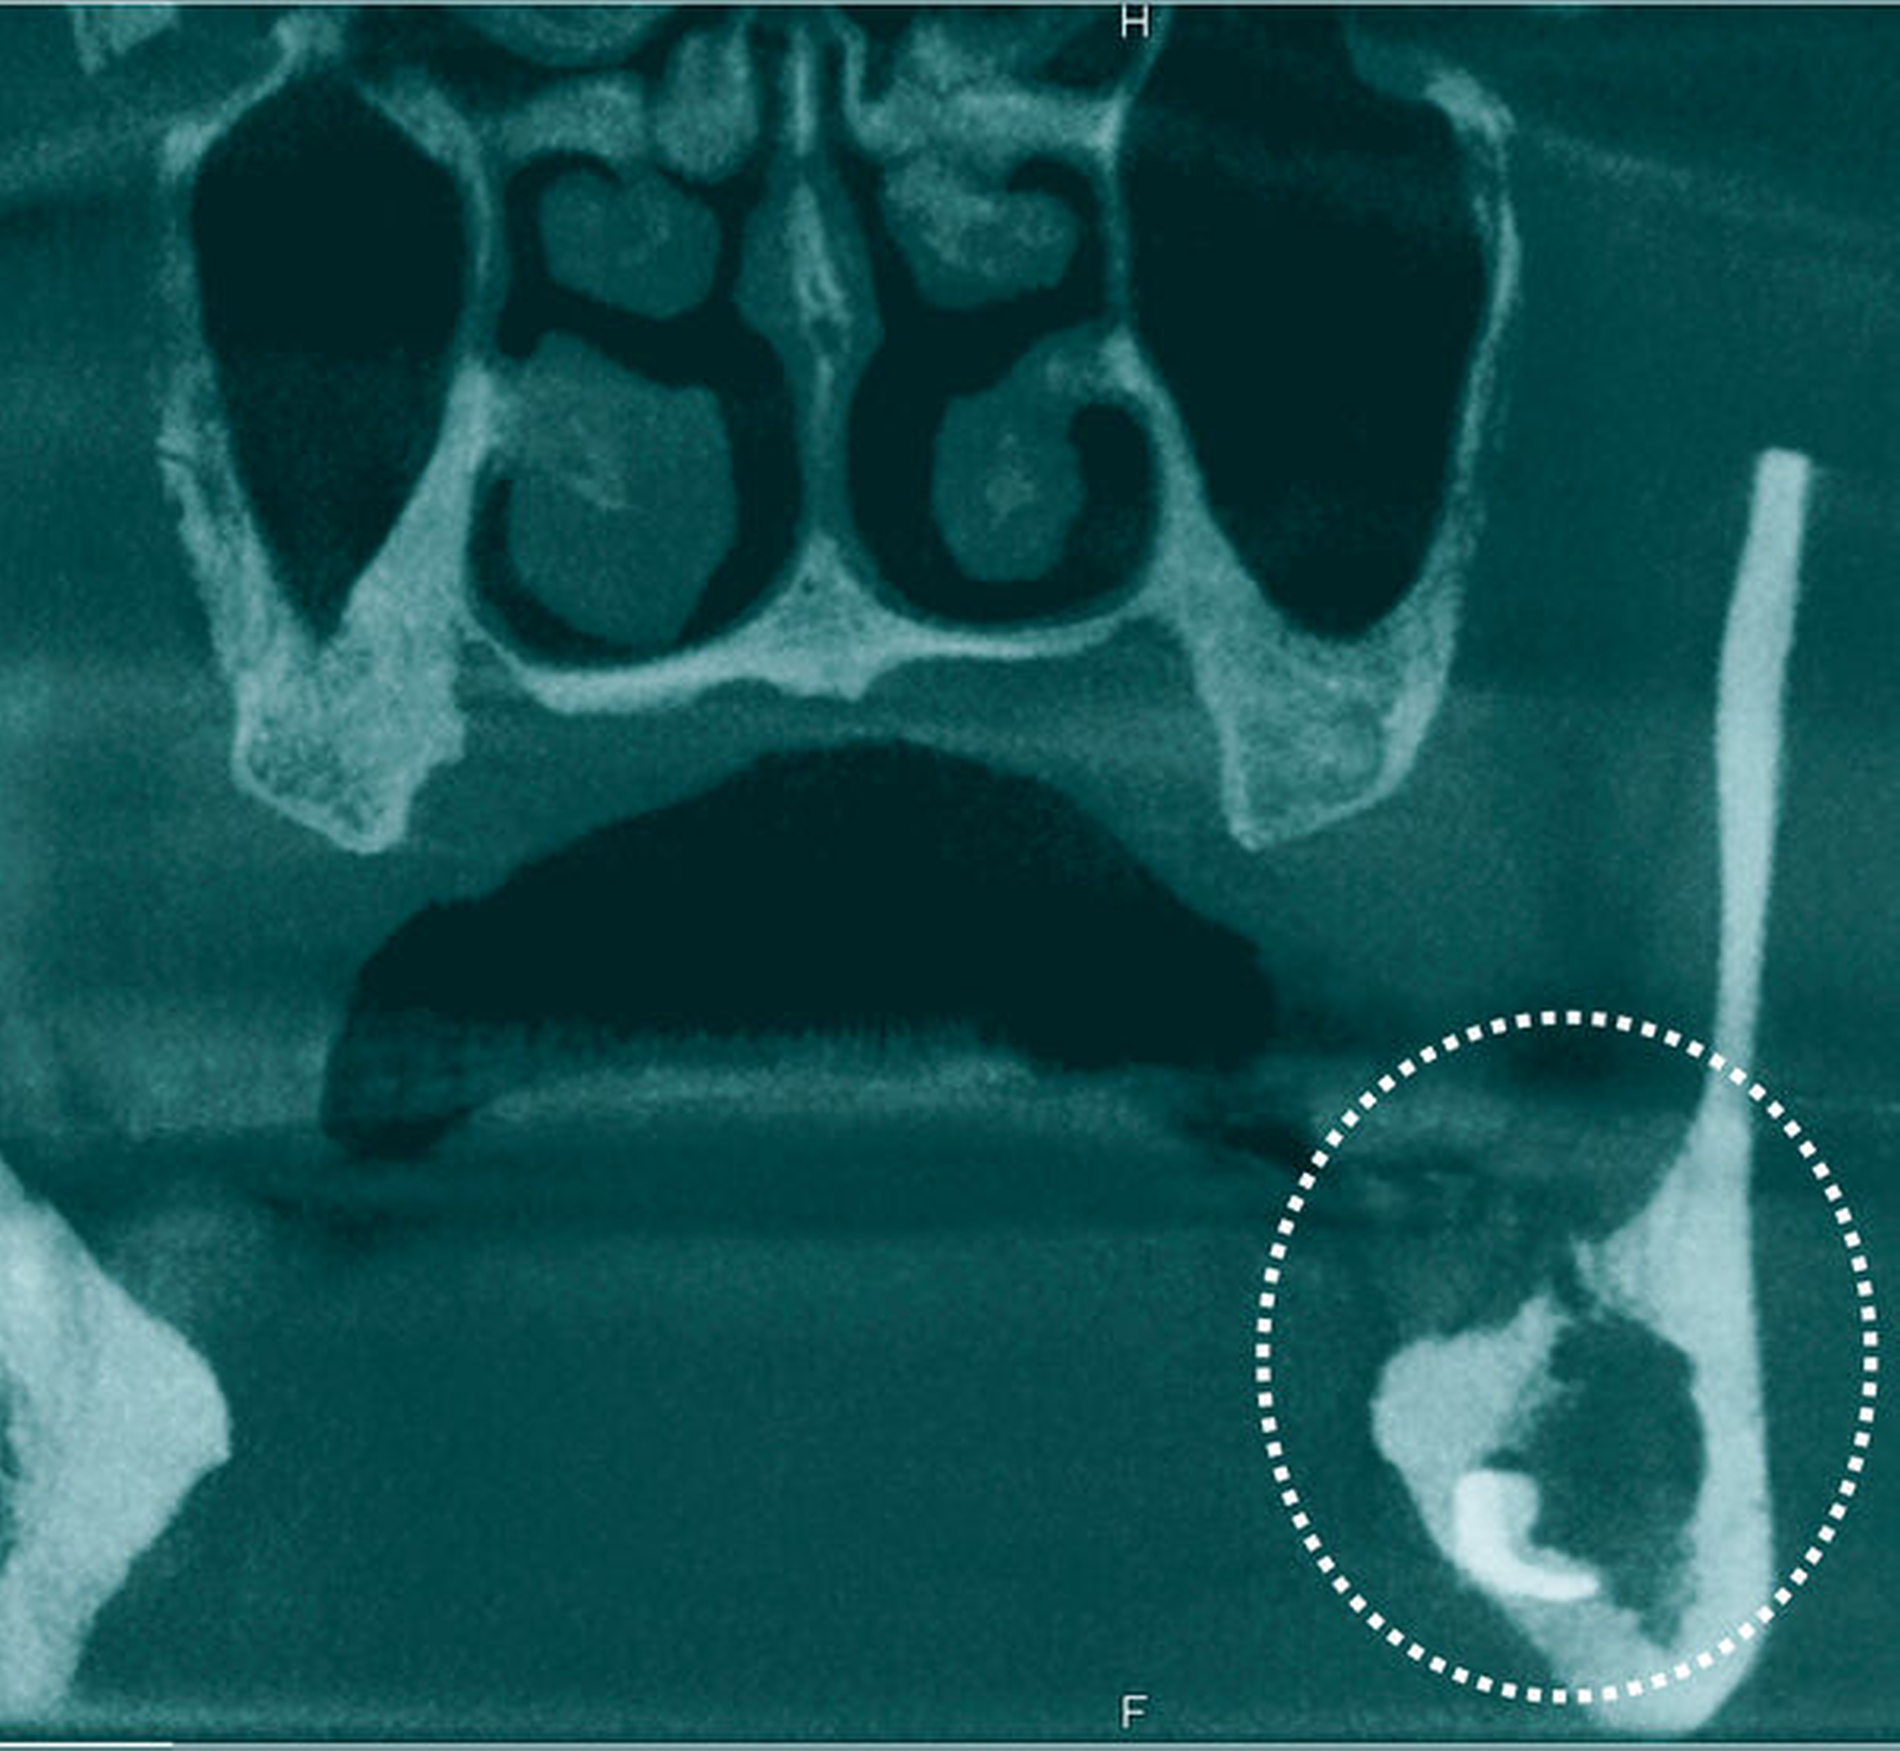

Aufgrund weiterhin zunehmender Beschwerden sowie einer klinisch und laborchemisch nicht rückläufigen Entzündungsproblematik erfolgte einige Tage später ein CT der Kopf-Hals-Region mit Kontrastmittel. Hier zeigte sich eine neu aufgetretene Abszessausbreitung in Richtung links submandibulär-anterior. Zusätzlich zeigte sich im Knochenfenster eine deutliche, ausgeprägte Osteolyse des gesamten linken aufsteigenden Unterkieferastes distal des Zahnes 37 bis hin zum Collum mit Beteiligung der nahezu gesamten Innen- und Außenkortikalis (Abbildung 2).